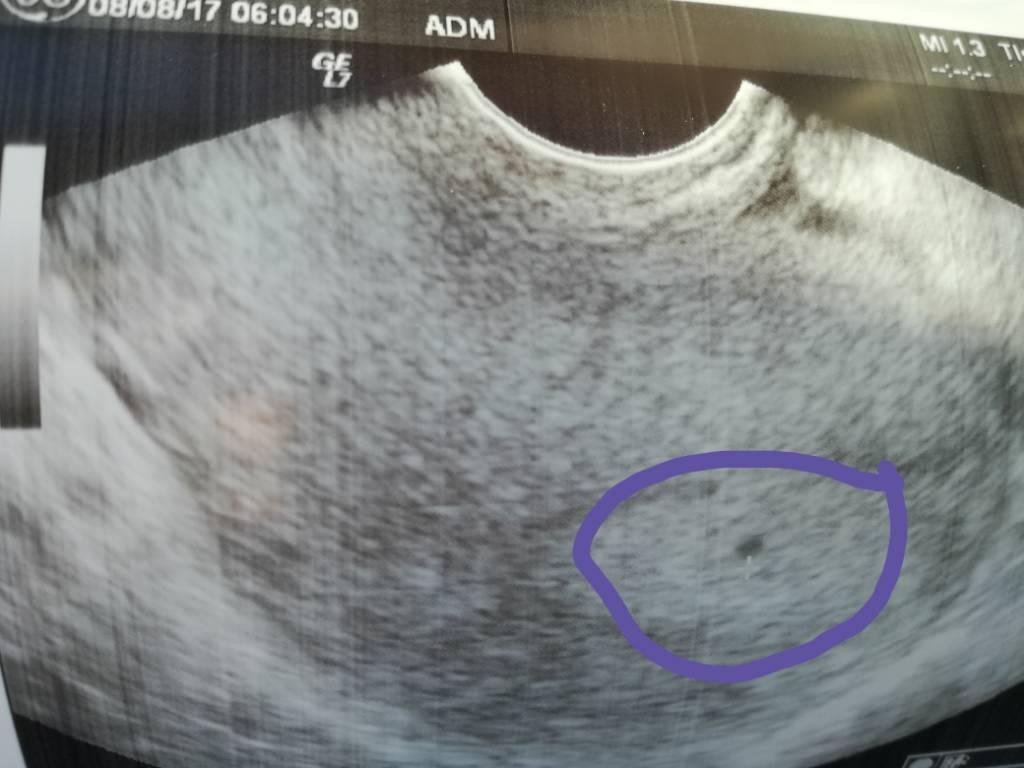

1502121923-aaaaaa.jpeg

Potwierdzona ciąża, ale nic więcej... nie zmierzył, nie zrobił zbliżenia, powiedział tylko że za 3 tygodnie przyjść. Żadnych badań nie dal... zdziwił się że W ogóle coś widać...

Cham jeden.... Dobrze że nie b będzie mi prowadził mojej ciąży